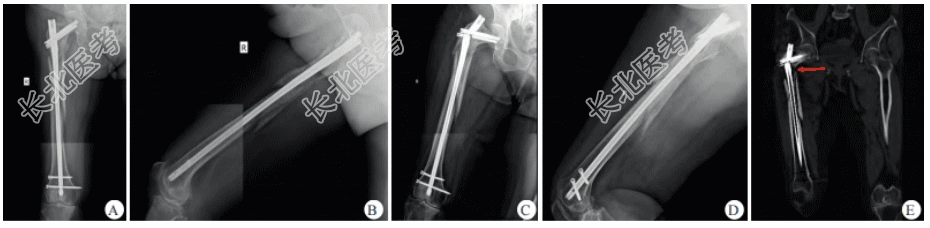

患者经对症支持治疗后生命体征趋于平稳,为便于多发伤后续诊治及护理,减少患者搬运及体位变动过程中骨折所致副损伤,经多学科会诊讨论后决定行右股骨转子下骨折手术治疗。患者经支持治疗后生命体征恢复平稳,但血红蛋白、血小板及白蛋白仍处于较低水平,应避免过大的手术创面,故手术方案拟选择闭合复位InterTAN髓内钉固定术。术后因患者体位难以配合,仅行右股骨正位X线检查,示InterTAN髓内钉位置良好,但骨折断端仍残留间隙(图1B)。由于患者转子下骨折粉碎严重,术后骨折断端残留明显间隙,为避免内固定松动移位,术后8周患肢开始部分负重功能锻炼,术后3个月患者可扶拐行走,术后5个月复查X线片示InterTAN髓内钉位置良好,骨折端形成骨痂(图2A、图2B)。术后21个月,患者主诉正常行走时无明显诱因出现右髋部疼痛伴活动受限、无法行走。右股骨正侧位X线检查示髓内钉主钉、加压螺钉及远端锁钉均出现断裂(图2C、图2D);进一步行去金属伪影CT检查,示股骨颈干交界部位骨折不愈合(图2E)。

患者因InterTAN髓内钉断裂而丧失正常行走能力,且患肢活动时伴有明显疼痛。由于断裂的残钉挤占了骨折不愈合部位植骨空间,遂决定使用接骨板螺钉(髓外固定)行翻修手术。